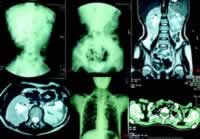

排尿困难、脓血尿、肾功能不全

患儿1个月前无诱因出现排尿困难及无力,尿线细小,伴全身乏力消瘦。曾到当地医院就诊,做肾盂静脉造影提示一侧肾萎缩,肾结核,给予异烟肼、利福平治疗十余天后家属自行停药。入院前3天,患儿厌食、乏力加重,出现恶心、呕吐,为非喷射性呕吐,呕吐胃内容物。尿量较前明显减少(150~300 ml/d),尿液混浊,可见血丝、血块及絮状物。至入院当天,已24小时无尿。入院前在当地医院检查:尿常规示红细胞(RBC)、白细胞(WBC)满视野,上皮细胞5~10/HP,蛋白150 mg/d;尿素氮(BUN)50.63 mmol/L,肌酐(Cr)803 μmol/L,钾 5.82 mmol/L,钠 126 mmol/L。胸片示多发肺囊肿合并感染。为进一步治疗以“肾功能不全、多发肺囊肿”收入我院。

血常规:WBC 16.8×109/L,中性粒细胞 88.9%,淋巴细胞8.3%,血红蛋白 140 g/L,血小板560 ×109/L;尿常规:外观黄色混浊~血性,尿蛋白++,潜血+++,镜检RBC 15~20/HP,WBC 25~30/HP;血气分析(入院时):pH 7.173,二氧化碳分压(PCO2)21.4 mmHg,HCO3- 7.9 mmol/L,二氧化碳结合力(CO2CP)6.3 mmol/L,碱剩余(BE)-21 mmol/L;血生化(入院时):K+ 6.48 mmol/L,Na+ 120 mmol/L,Cl- 80 mmol/L,BUN 57.9 mmol/L,Cr 911 μmol/L,Ca2+ 2.3 mmol/L,P 4.6 mmol/L,Mg2+ 1.43 mmol/L,天冬氨酸氨基转移酶(AST)17 U/L,丙氨酸氨基转移酶(ALT)9 U/L ......